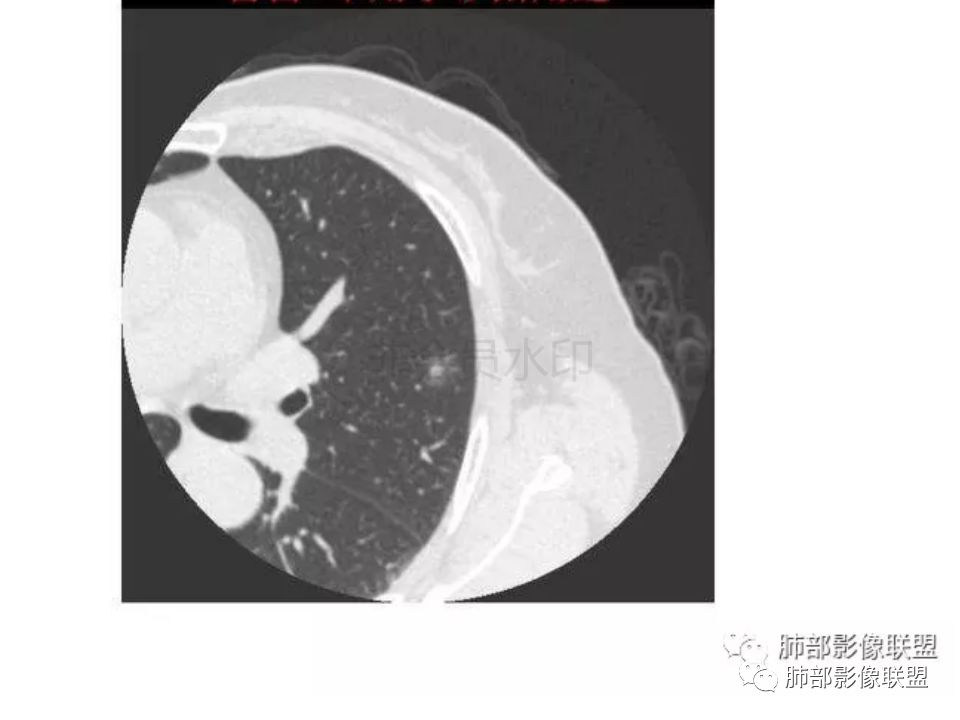

【每日晨读】腺癌VS隐球菌

三生石上:支气管有截断,周围有晕,有空泡,腺癌?毛勤香:左肺下叶近胸膜下结节,周围磨玻璃影,边界似稍模糊,局部细支气管截断,实性区和磨玻璃区分界突然,隐约细毛刺,首先考虑感染性,隐球菌?待排腺癌MIA伴肺泡塌陷可能。常规治疗后复查。Coke with ice:IACM-Imaging :孤立胸膜下结节,其内见小泡,周围模糊的晕,晕中软毛刺,近端与血管相连,血管自然通过,气管进入结节内部一半,猜个隐球吧。第二腺癌,建议复查。田园晚风:考虑腺癌紫气东来:左肺上叶,磨玻璃实性毛刺,空泡,支气管截断,腺癌雪颜:左肺上叶结节状密度增高影,周围有晕,感觉周围模糊,有血管进入,里面有空泡征,隐约看到里面有支气管穿过,考虑炎性,隐球菌感染?腺癌待排THINKER:上叶尖后,SPN,有晕,软毛刺,无胸膜凹陷,分叶丶收缩不明显,支气管进入,远端阻塞,首选肉芽肿,PC或炎性结节,有一支血管滋养,鉴别腺癌,增殖性结核结节不支持期:左上肺结节周围有晕 晕中见细软毛刺 首先考虑隐球菌一米阳光:左肺上叶磨玻璃影,空泡,周围毛刺,月牙铲,支气管通过,周围有晕,考虑腺癌我的FY:毛刺,小空泡,磨玻璃考虑恶性崔少钢:小病灶,内有支气管,空泡征,实变不规则,放大了,感觉晕有点偏清,考虑恶性。小病灶里面有支气管是值得高度怀疑的。没有病史。彭君:左肺上叶舌段结节 周围晕模糊 内小支气管扩张 近端与血管相连 自然通过 首先考虑炎性 隐球菌?边缘月牙铲 腺癌待鉴别徐婕:左上肺结节周围有晕 ,晕中见细软毛刺 ,晕边界不太清,先考虑隐球菌张帅:左肺上叶尖后段实性病灶,以细支气管为中心,周围呈毛玻璃样影,并可见密集分布毛刺,内可见支气管征,支气管呈壁呈结节样改变,病灶周围可见血管增粗。考虑 淋巴瘤?鉴别隐球。张延军:混合型磨玻璃结节,伴毛刺,支气管截断,空泡,考虑浸润性腺癌,建议抗炎治疗后复查XGQ:支持隐球春秋:结节伴晕征,晕中毛刺,相邻小支气管近端进入,远端阻塞,近端血管相连,首先考虑隐球菌王秀仙:左肺上叶混合型磨玻璃结节,支气管截断,空泡,有毛刺,考虑浸润性腺癌,建议抗炎治疗后复查玫:左肺上叶磨玻璃结节影,薄扫见长短不一毛刺,有空泡,病灶边缘见晕征,考虑小腺癌可能,不除外炎性结节。zyf:左肺下叶近胸膜下结节,周围有晕,细软毛刺,有支气管进入,实性区和磨玻璃区分界明显,首先考虑感染性,隐球菌?查隐球菌荚膜抗原!RockJ-ason:考虑隐球采莲:左上肺靠近胸膜下实性结节影,边缘模糊,周围有晕及晕中毛刺,支气管进入通畅,有小空泡。考虑炎性病变,隐球可能性大。鉴别结核。Harvey:左肺下叶舌部小结节,边缘见磨玻璃影,边界欠清,内见支气管、管壁不光整,偏向恶性。鉴别隐球菌lmg:左肺上叶混合小结节,有晕,边界模糊,有有小毛刺。考虑炎性病变,隐球收选。AIS并肺泡塌陷带排。山河:倾向腺癌红日东升:GGO边界似清非清,内部好像不是小空泡,是小支气管腔,倾向炎性病变,常规抗炎复查除外腺癌,尤其粘液腺癌。

我怎么感觉支气管是通的,周围的晕又比较软,我考虑炎性病变,隐球菌可能大(如下图)

隐球菌感染孤立病灶与肺腺癌结节在影像上有时难分彼此,尽管隐球菌胸膜下更常见。

1.隐球菌病灶往往是实性密度结节为主伴周边边界不清楚的晕,有时可见晕内细软毛刺。

微浸润腺癌常常是磨玻璃密度为主的结节,边界比较清楚,并似乎有弧线形小叶间隔阻挡的痕迹。

实性结节的腺癌则很少有磨玻璃晕,往往会有粗短的硬毛刺。

2.隐球菌病灶形态往往圆钝柔和,缺乏收缩能力,很少出现腺癌的那种胸膜牵拉和棘状突起。

3.病灶内支气管安然无恙隐球菌病灶更加多见

4.隐球菌病灶增强扫描可轻度强化。既不同于结核灶的几乎不强化,也不同于肺腺癌的明显强化。

该患者实性成分为主,可惜未提供增强扫描图像。